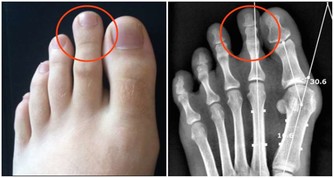

鞋子穿久了腳指甲通常會有內翻的情況,又稱指甲內生,

但其實正確來說是「甲溝炎」、「凍甲」。

當這個情況發生的時候,因為指甲會夾到肉,感覺非常痛。

如果狀況比較糟糕的話,會發生發炎、化膿的情況,而且會痛到讓人無法走路喔!